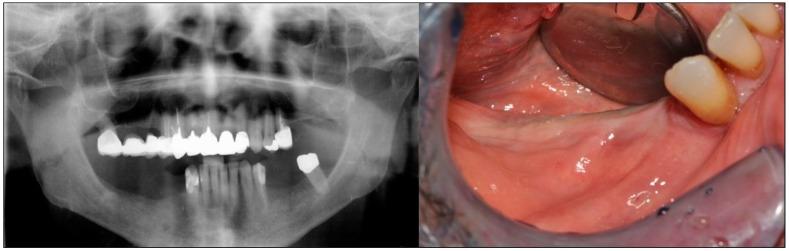

One of the most often used bone augmentation techniques is the guided bone regeneration procedure. The authors report the case of a 75-year-old man with an atrophic right posterior mandible who underwent bone augmentation through guided bone regeneration with a preshaped titanium mesh adapted on a stereolithographic model of the patient's jaw. The graft volume was simulated with a light-curing resin. The actual site was grafted with a mixture of autogenous and equine-derived bone. Five months later, the mesh was retrieved, three cylindrical implants were positioned, and a bone biopsy was collected for histomorphometric analysis. A provisional prosthesis was delivered three and a half months later. Definitive rehabilitation was accomplished after one additional month. The graft allowed for effective bone formation (newly formed bone, residual biomaterial, and medullar spaces were, respectively, 39%, 10%, and 51% of the core volume). The patient has functioned successfully throughout six and a half years of follow-up. Using the preshaped titanium mesh in association with the enzyme-treated equine bone substitute provided effective bone regeneration.

最常用的骨增量技术之一是引导骨再生术。作者报告了一例75岁男性患者,其右侧下颌骨萎缩,通过引导骨再生术进行骨增量,使用了根据患者颌骨的立体光刻模型定制的预成型钛网。用光固化树脂模拟移植骨体积。实际部位植入了自体骨和马源骨的混合物。五个月后,取出钛网,植入3枚圆柱形种植体,并采集骨活检样本进行组织形态计量学分析。三个半月后安装临时义齿。再过一个月完成最终修复。移植骨实现了有效的骨形成(新形成的骨、残余生物材料和骨髓腔分别占核心体积的39%、10%和51%)。在六年半的随访期间,患者功能良好。使用预成型钛网联合酶处理的马骨替代物可实现有效的骨再生。